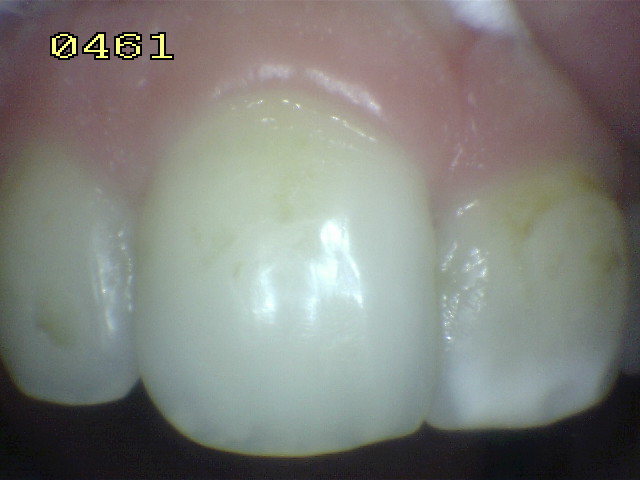

Una morfología de la fisura estrecha, con forma de botella de "Coca-Cola" genera un nicho ecológico ideal para la colonización de cualquier bacteria productora de ácidos. Al no poder remover en forma períodica dicho biofilm de una zona tan estrecha, el ataque ácido genera una lesión cariosa en la dentina, con un aspecto de esmalte intacto a la inspección visual, o sea un típico código 3 y 4 de ICDAS Completo. (Caries Moderada para el ICDAS COMBINADO)

Imagen digital que representa la microfiltración y penetración del sellante realizado.

Microfotografía: Muestra como el sellador obtura la caries subyascente, evitando su avance.

Código 3 (Caries moderada) in vitro. Los códigos 3 in vivo debe ser sellado para evitar el avance del proceso carioso. (MNO)

Código 4 (Caries moderada) in vitro. Los códigos 4 in vivo deben ser tratados en forma operatoria con preservación dental (MOPD), porque presentan dentina infectada.